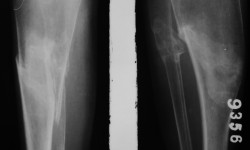

OSTEOPETROSIS (Tarda) WITH FRACTURE By Admin | October 1, 2013 - 2:17 pm | Musculoskeletal, Skeletal Dysplasias Leave a comment Fig.1 Fig.2 Fig.3